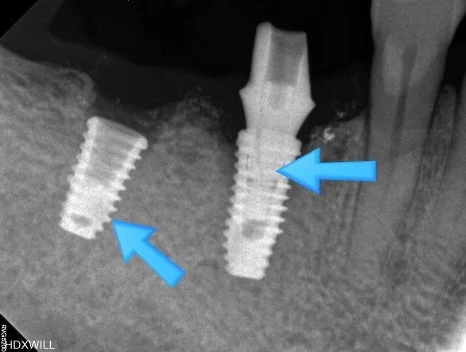

화살표로 표시된 부분을 보면 왼쪽은 내부에 무언가 남아 있는 것처럼 보이고, 오른쪽은 금이 간 듯한 모습이 확인됩니다.

정확한 상태를 확인하기 위해 우측 사진에서 가운데 지대주를 제거한 뒤 다시 촬영을 진행했습니다.

그 결과 화살표로 표시된 부분을 보면 왼쪽 임플란트는 나사 부위가 부러져 있었고, 오른쪽 임플란트는 본체에 금이 생긴 상태였습니다.

처음 임플란트가 흔들리는 느낌이 있었을 때 바로 내원하셨다면 다른 부속 부위까지 손상되기 전에 적절한 처치를 받을 수 있었을 가능성이 있습니다.

결국 두 임플란트 모두 제거한 뒤, 위 사진과 같이 본원에서 다시 임플란트 치료를 진행하게 되었습니다.